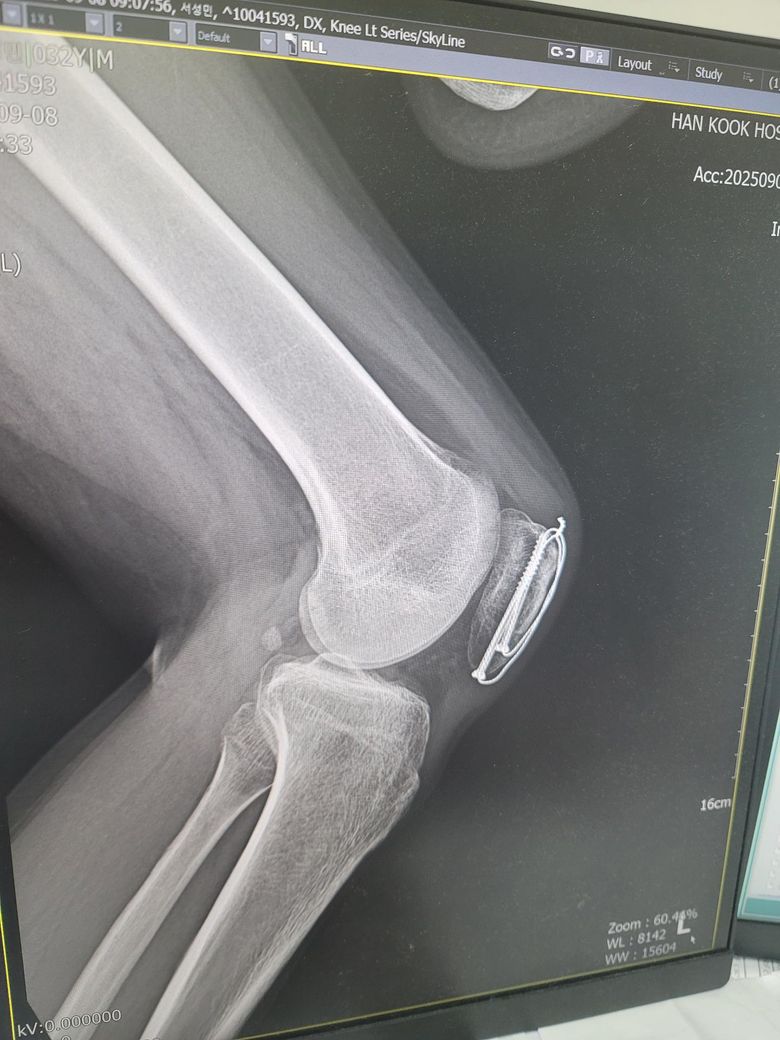

슬개골 수술후 엑스레이입니다 엑스레이상 핀제거도 가능한거겠죠? 어렵거나 못빼진않는거죠? 핀 한개위치나 뼈속안에있어보여서요

핀 두 개 모두 뼈 안쪽으로 살짝 들어간 건 정상 위치이고, 뼈 속 깊이 박혀 있는 게 아니라 표면 가까이에 고정된 상태라 제거 가능합니다. 핀제거는 일반적으로 어렵지 않은 수술입니다. 단 수술 경과나 유착의 정도에 따라 달라질 수 있으니, 의사 선생님께 정확히 물어보시는 것이 가장 정확합니다.